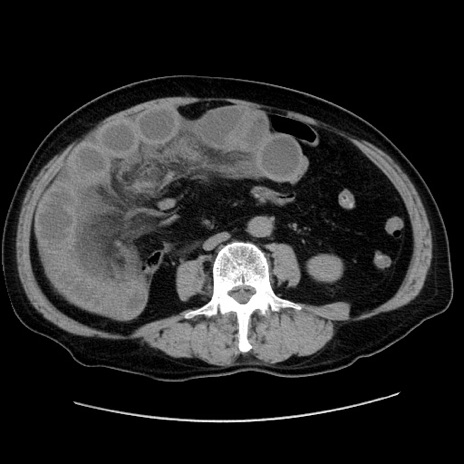

症例30(横断像)

【症例】80歳代男性

【主訴】臍周囲痛

【現病歴】約6時間前から臍下部痛が出現。次第に腹部膨隆・背部痛も生じてきたため来院。背部痛の場所は変化しない。

【身体所見】意識清明、BT 36.3℃、BP  131/87mmHg、P 87bpm、SpO2 100%(RA)、臍周囲自発痛・圧痛あり、反跳痛なし、自発痛部位に一致して板状硬あり、腹部膨隆、腸雑音減弱、CVA tenderness両側陰性。

【データ】WBC 19600、CRP 0.33